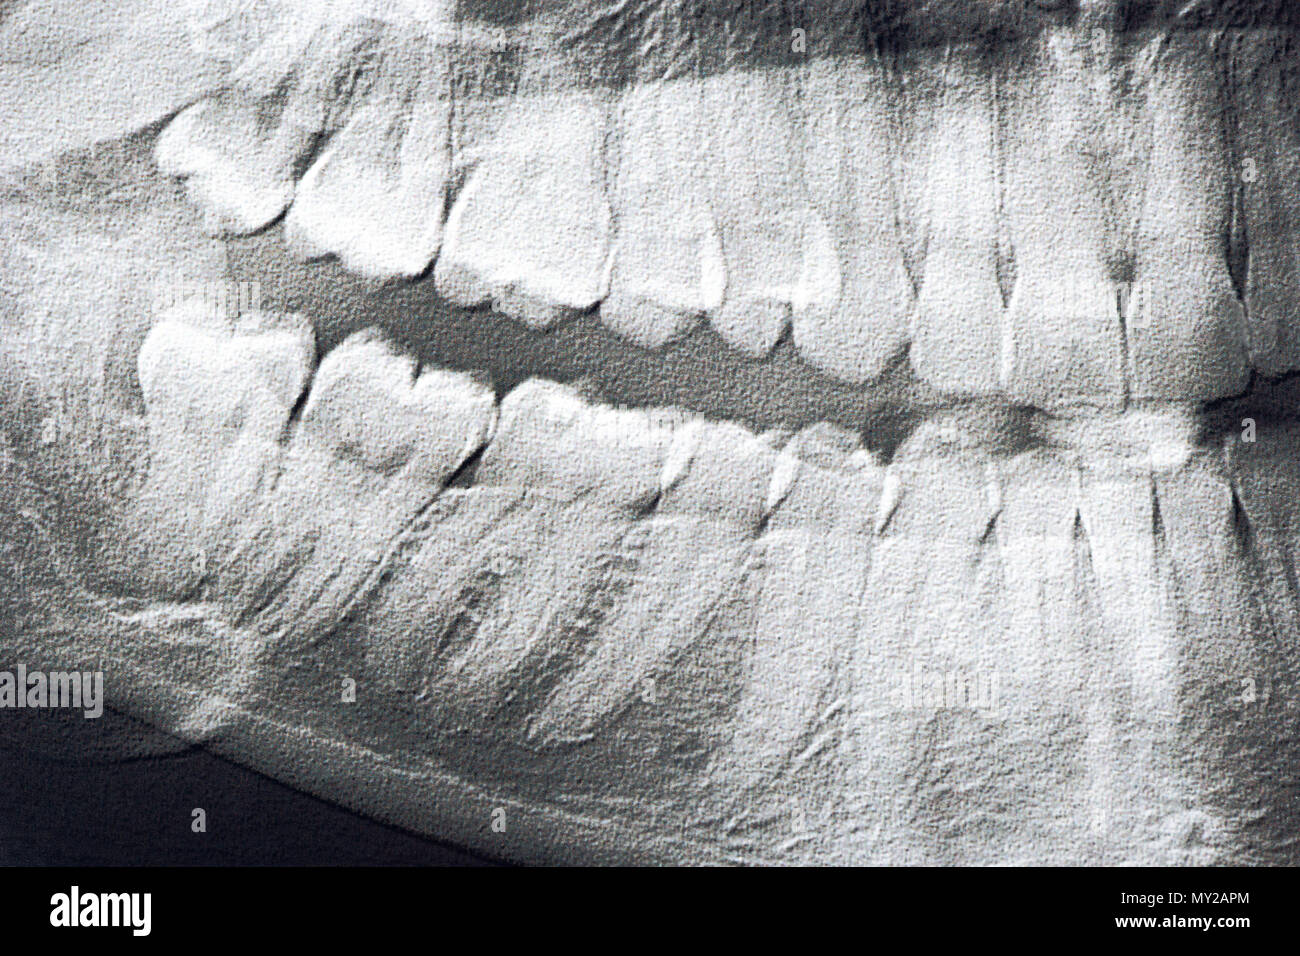

From www.sciencephoto.com

Normal lower jaw, Xray Stock Image F001/2999 Science Photo Library Jaw X Ray Views The temporomandibular joint (tmj) is a bilateral synovial articulation between the mandible and skull base. Proper characterization of jaw abnormalities is essential to ensure appropriate patient care and reduce morbidity. Imaging plays a key role in the characterization of a variety of jaw lesions, and radiologists must be familiar with A properly positioned radiograph of the face and mandible shows. Jaw X Ray Views.